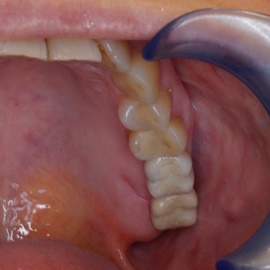

Hybrydowe podparcie protezy ruchomej na jednym implancie i jednym własnym zębie. Nie zawsze możemy osadzić u pacjenta dwa implanty. Przykłady hybrydowego podparcia protezy ruchomej na atachmentach opartych na własnym zębie i implancie.

Pacjent lat 68, po zawale mięśnia sercowego. Podczas reanimacji wyłamano ząb 43, będący zębem klamrowym szkieletu. Doszło do znaczącego ubytku tkanki kostnej. Osadzono implant, odbudowano brakujące tkanki kości i dziąsła. Pacjent zadowolony z hybrydowego zakotwiczenia protezy.